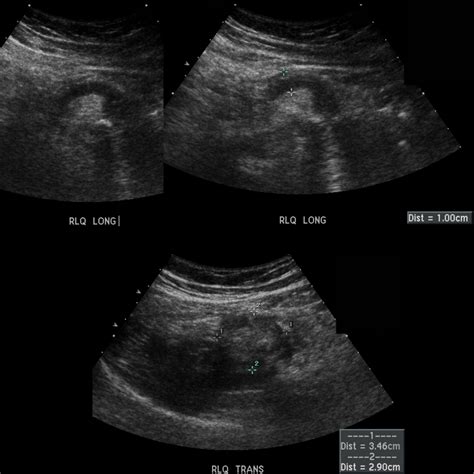

• Imaging: Ultrasound, CT scan, or X-rays to visualize the internal organs.